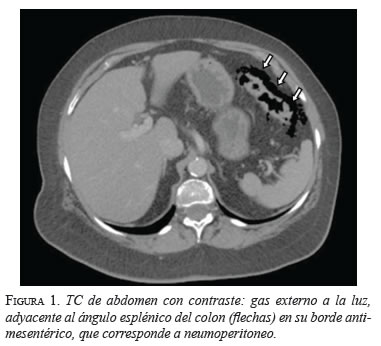

De los 60 pacientes que ingresaron con diagnóstico de diverticulitis, 3 (5 %) presentaron neumoperitoneo sin ningún otro hallazgo radiológico asociado (figura 1). Los tres eran del sexo femenino, con una media de edad de 67 años (rango: 61 a 72), y presentaban dolor abdominal progresivo en el hemiabdomen izquierdo que había aparecido tres a cinco días antes de consultar al servicio de urgencias,

En las tres pacientes, la TC abdominal con contraste mostró el neumoperitoneo pericólico o localizado a menos de 5 cm del asa inflamada sin aire distante (figuras 2 y 3); dos presentaron divertículos en el ángulo esplénico, colon descendente y sigmoide, y una en el colon sigmoide únicamente.